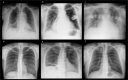

Chest radiographs allow for the meticulous examination of a patient's chest but demands specialized training for proper interpretation. Automated analysis of medical imaging has become increasingly accessible with the advent of machine learning (ML) algorithms. Large labeled datasets are key elements for training and validation of these ML solutions. In this paper we describe the Brazilian labeled chest x-ray dataset, BRAX: an automatically labeled dataset designed to assist researchers in the validation of ML models. The dataset contains 24,959 chest radiography studies from patients presenting to a large general Brazilian hospital. A total of 40,967 images are available in the BRAX dataset. All images have been verified by trained radiologists and de-identified to protect patient privacy. Fourteen labels were derived from free-text radiology reports written in Brazilian Portuguese using Natural Language Processing.